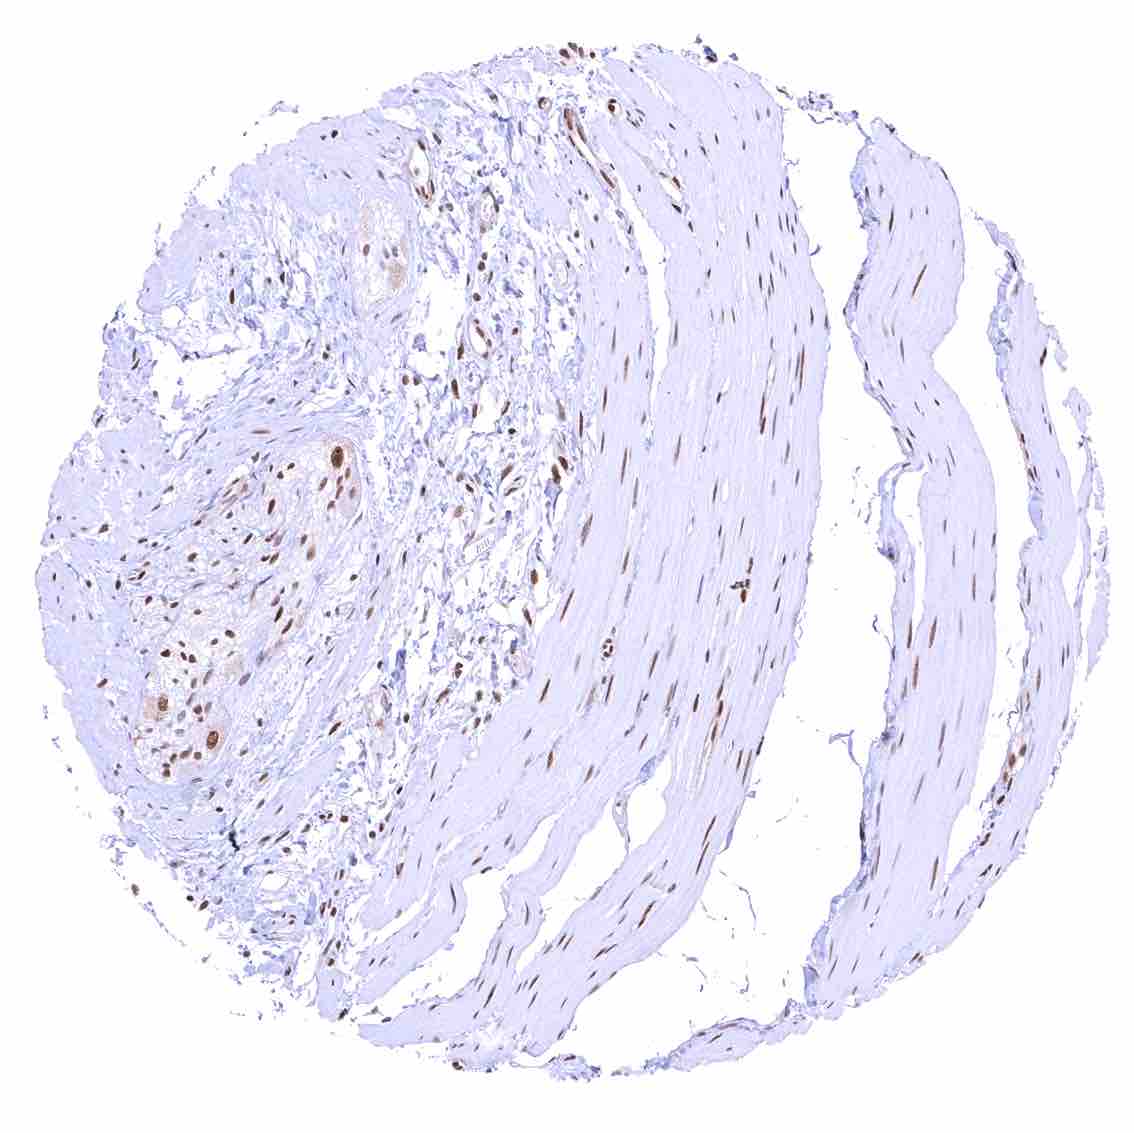

Aorta, media – Strong nuclear p27 staining of muscle cells in the aorta.